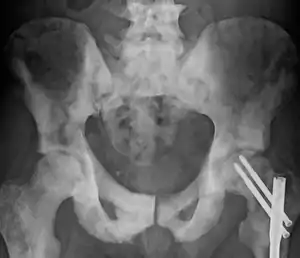

![]() | |

| Sclerosis of the bones of the pelvis due to prostate cancer metastases | |